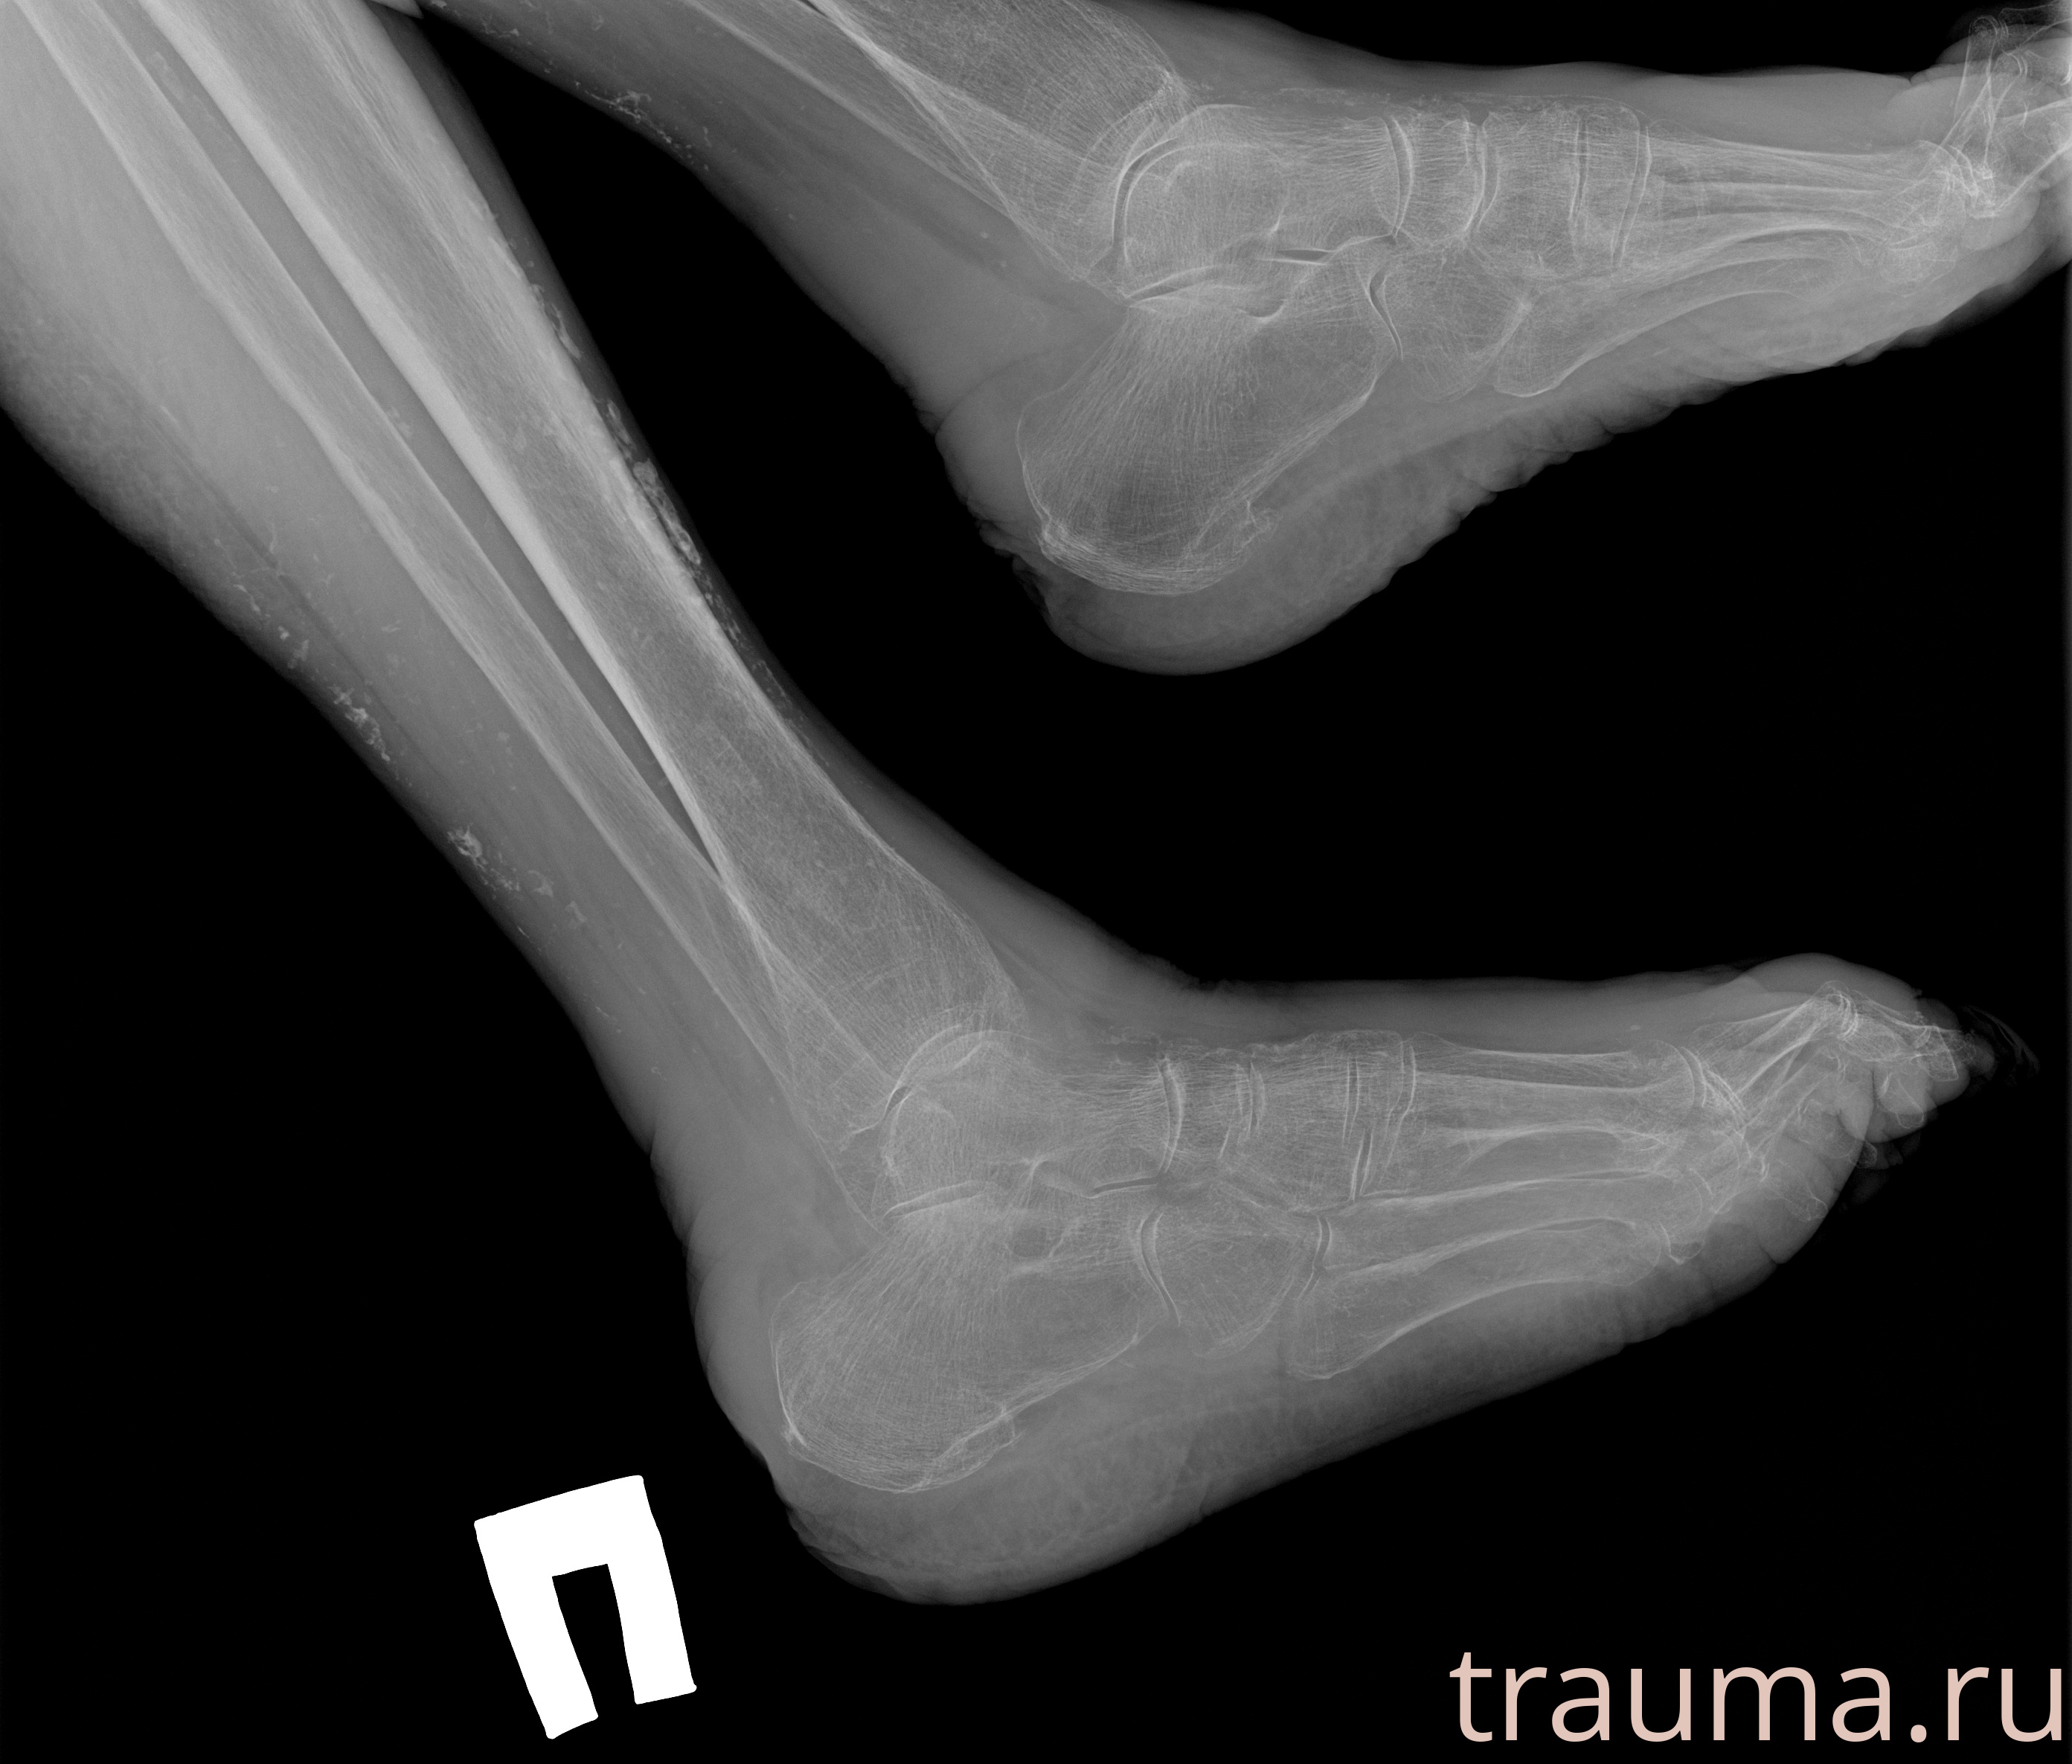

Рентгенограммы

Рентген на дому: по вашему адресу приезжает врач-рентгенолог, травматолог-ортопед с мобильным рентгеновским аппаратом, проводит диагностику травмы или заболевания, делает необходимые рентгенограммы, дает рекомендации по дальнейшему лечению. Получить качественные снимки в домашних условиях возможно благодаря уникальной методике, разработанной МосРентген Центром для института  Склифосовского